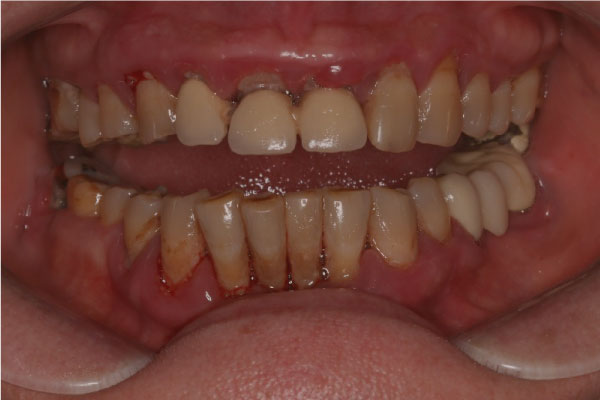

Имплантация зубов: фото "До" и "После"

Фото ДО

Фото ПОСЛЕ

Наведите для просмотра

All-on-4